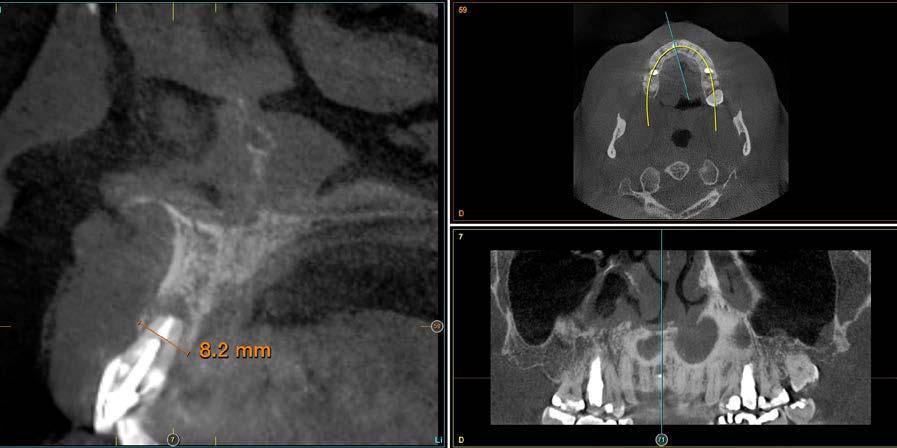

radiografía panorámica inicial para el diagnóstico nos aporta una imagen radiolucida entorno al ápice del diente en posición 11 ( Figura 1 ). Para conocer mejor el alcance de la lesión y las opciones terapéuticas de las que disponemos se lleva a cabo un cone-beam en el que se puede objetivar de forma precisa el defecto apical al diente. Este defecto es circunferencial y está dejando una reabsorción casi completa de la tabla ósea vestibular y parcial de la palatina, con un grosor de 1.9 mm, como vemos en el corte seccional (Figura 2). Si observamos la medida total en la zona media del incisivo dentral, necesitamos cubrir una anchura aproximada de 8 mm por lo que el implante que coloquemos irremediablemente dejará un gap, que según los protocolos quedará en vestibular. Utilizando una plataforma estándar de 4.1 mm el gap a rellenar será prácticamente de 4 mm según las medidas que nos

Figura 2. Corte seccional del cone-beam

arroja el cone-beam de planificación. Utilizaremos además un implante de longitud mayor que la que se emplearía para un incisivo central en una zona edéntula, para lograr un anclaje apical que nos dé la estabilidad necesaria en la colocación del implante y

nos permita la carga inmediata posterior. En este caso 11.5 mm (Figura 3 y 4).Una vez diagnosticado el caso de forma correcta con las imágenes del cone-beam iniciamos la fase quirúrgica. Realizamos la exodoncia del diente 11 con el menor trauma